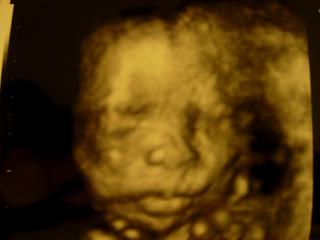

@jankaslamka veľmi podarený záznam, všetko veľmi pekne vidno a tá pusinka na spapkanie 🙂)

@jankaslamka jeej nádherne miminko gratulujem a tisko zavidime my ideme až v januári 😎

@majulienka27 jeej dakujem 🙂 ta pusina je uzasna...sa neviem vynadivat 🙂

@honeybunny81 dakujeem 🙂 neboj potom ja budem tebe zavidiet lebo to ja uz budem mat pocit, ze je to davno co som videla babo a zas daleko do dalsieho ultrazvuku kedy ju zas uvidim 🙂 a takto ju vlastne uvidim az nazivo..takze nech uz je maj 🙂